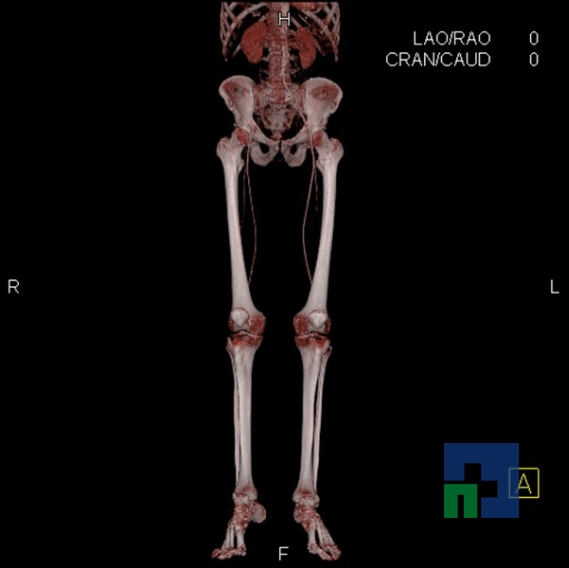

Examinare de rutină cerebrală, nativ și cu substanță de contrast (SDC) pentru diagnosticul:

În cazul traumatismelor cranio-cerebrale:

- Diagnosticul traumatismelor de bază de craniu